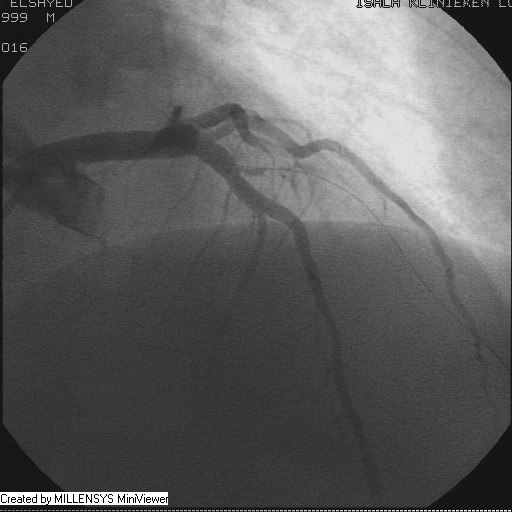

Patient transfered to Cardiac Catheterization Laboratory, coronary angiography showed atherosclerotic coronaries but without significant lesions, especially LAD that was patent with TIMI 3 flow (Figure 1- 5). Re-evaluation of the Angiography showed a small stump that can be for an occluded 1st diagonal (Figure 2a), at that level the LAD has a non-significant lesion.

Figure 3

Figure 4